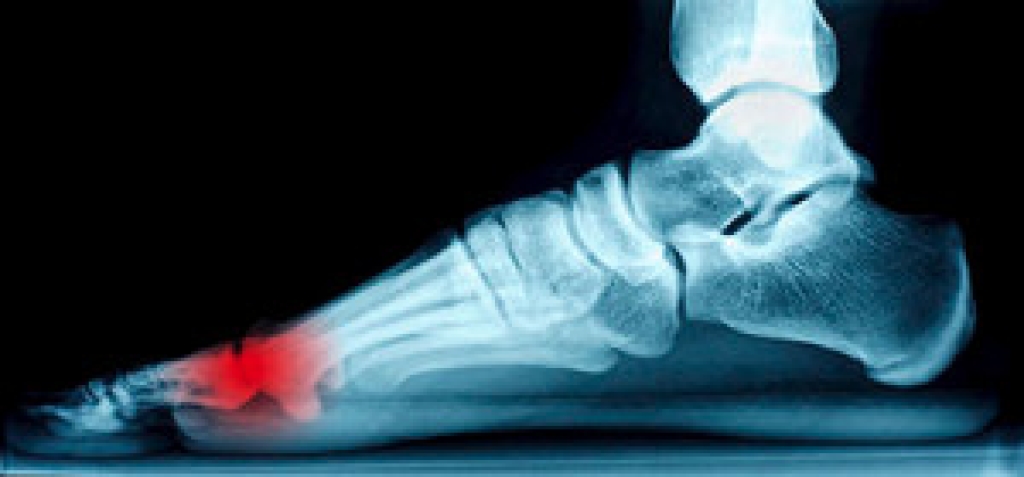

Foot reconstruction is a type of surgery that is performed to correct the anatomy of the foot and restore proper function. Someone might need reconstructive foot surgery following a major injury to the foot that affects the foot’s soft tissue or bones. Vascular diseases, which can interfere with circulation in the lower limbs, may require surgical intervention. Other issues which can cause deformities include metabolic diseases, such as diabetes and gout, that alter the blood and nerve supply of the foot, and tumors. Finally, birth defects such as clubfoot would also need to be corrected via reconstructive surgery. For more information on reconstructive foot surgery, please consult with a podiatrist.

Foot and ankle surgery is generally reserved for cases in which less invasive, conservative procedures have failed to alleviate the problem. Some of the cases in which surgery may be necessary include:

- Removing foot deformities like bunions and bone spurs

- Severe arthritis that has caused bone issues